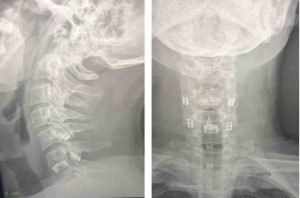

Cirugía realizada en hospital HM Puerta del Sur en Móstoles. Controles radiológicos de la intervención quirúrgica.

RX Control Artrodesis Columna Cervical

Tras la cirugía el paciente utilizó un collarín blando por un corto periodo de tiempo. Tres meses después de la intervención y tras algunas sesiones de rehabilitación, el paciente vuelve a su actividad laboral. No presenta dolor cervical. Tiene mínimas molestias con la extensión máxima del cuello. El hormigueo que presentaba previamente no ha desaparecido pero ha mejorado notablemente y no le incomoda.